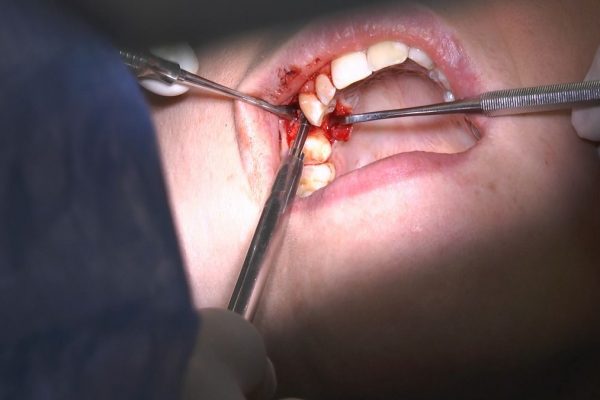

W ostatni weekend czerwca 2018 roku kursanci II Sezonu Preludium Implantologii odbyli piątą, finałową sesję, która w całości podporządkowana była praktyce. W ciągu dwóch dni zabiegowych Lekarze uczestniczący w szkoleniu przeprowadzili szereg zabiegów pod kierunkiem dr n.med. Violetty Szycik. Wszczepili 17 implantów oraz przeprowadzili ekstrakcje i zabiegi regeneracyjne kości. Zabiegi były wykonywane także w sedacji dożylnej z udziałem specjalisty anestezjologii i intensywnej terapii dr Jolanty Grzybowskiej. Preludium implantologii to nowy program edukacyjny dla adeptów implantologii stomatologicznej, którego celem jest wprowadzenie do implantologii poprzez pozyskanie wiedzy w szerokim zakresie i uwzględnieniem szczegółów mających decydujące znaczenie dla powodzenia leczenia implantologicznego. Ale tak jak wszystkie szkolenia w Instytucie Vivadental, w tym wiodące Practiculum Implantologii, zorientowane jest na praktyce i samodzielnym wykonywaniu zabiegów pod kierunkiem Mentora. To najlepsza edukacja w medycynie zabiegowej, a zarazem najlepszy start do implantologii.